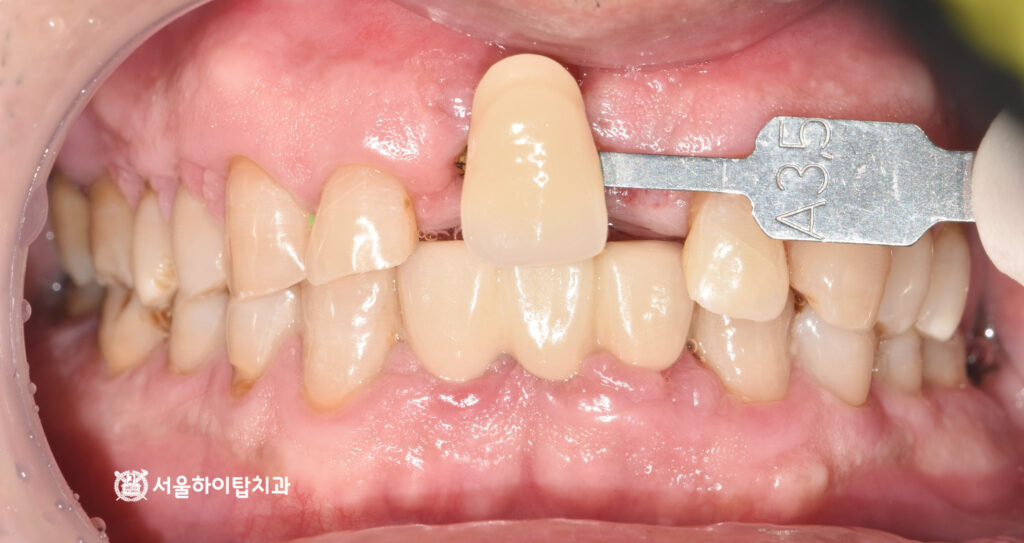

4. 임시 치아 제작

앞니는 위치 특성상 외부에

쉽게 드러나는 부위이므로

골 유착이 진행되는 동안

심미성을 유지할 수 있도록 미리

임시 치아를 제작하여 장착합니다.